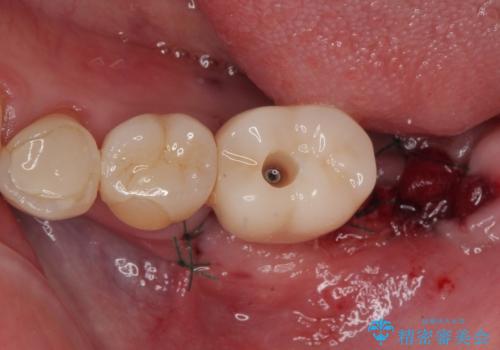

ブリッジから膿が出る 奥歯のインプラント治療

- ブリッジの土台から膿が出るとのことで来院された患者様です。

不均衡で無理な力がかかってしまうブリッジを装着したため、最後臼歯周辺の歯槽骨が溶けている状態でした。

上顎は最後臼歯が欠損しているため、ブリッジの土台は抜歯し、元々の欠損部にインプラントによる補綴治療を行うこととしました。

支台歯の骨欠損は予想以上に大きく、即時荷重インプラント部への影響が心配されましたが、無事に最短期間で治療を終えることができました。